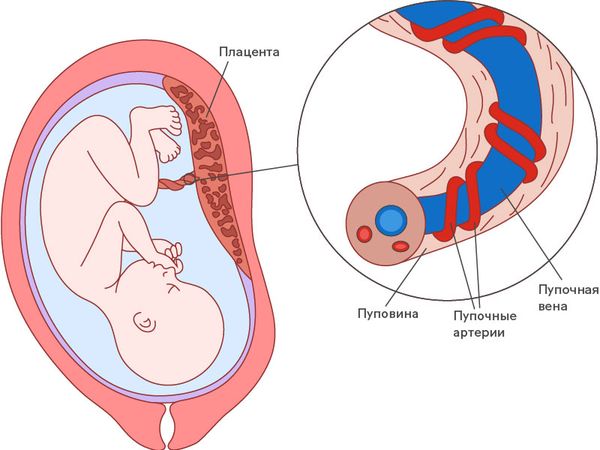

Пуповина (пупочный канатик; канатик жизни) — это шнуровидное образование, которое соединяет пупочную область плода с плацентой (детским местом) и состоит из сосудов, несущих кровь от плода к плаценте и обратно. Пуповина анатомически входит в состав последа (того, что рождается после младенца).

В норме пуповина представляет собой винтообразный, скрученный слева направо канатик, внутри которого расположены три сосуда: одна вена и две артерии. Число витков пупочного канатика зависит от его длины и может разниться от 10 до 25 [8].

Строение пуповины

Сосуды пуповины окружены веществом, которое называют вартоновым студнем. Оно играет важную роль: обеспечивает упругость пупочного канатика, предохраняет пуповину от сдавления, осуществляет обмен веществ между кровью плода и околоплодной жидкостью [4]. Диаметр сосудов пуповины постоянен, меняется только толщина вартонова студня.